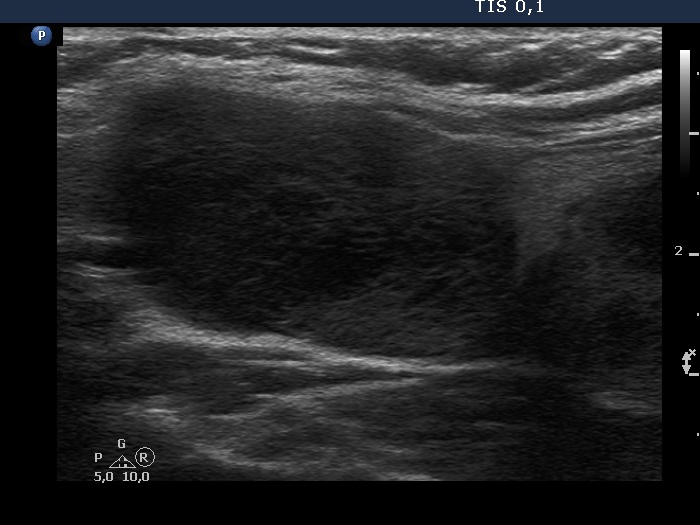

First examination (first, third and fifth rows of images):

Ultrasonography. The thyroid was echonormal and contained multiple inhomogeneous, partly blurred hypoechogenic and moderately hypoechogenic discrete lesions. Multiple lymph nodes were found on both sides of the neck.